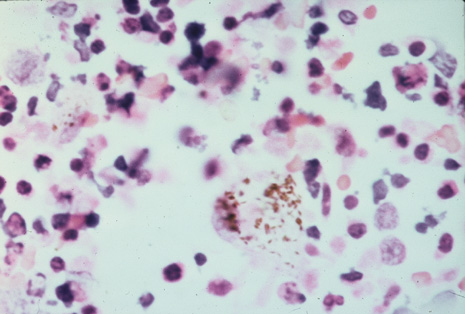

Many forms of uveitis are characterized by specific types of inflammatory cells. Usually, however, one encounters mixtures of cell types in any given specimen, with the relative percentages of lymphocytes and polymorphonuclear leukocytes varying. There may be unusual numbers of eosinophils, or macrophages laden with lens material may be present. Thus, an enumeration of the cells and a careful analysis of their structure can be useful as a diagnostic aid (Figs. 7, 8, 9, 10, 11, 12, 13, 14, 15, 16, 17, 18, 19, and 20). Figure 15 demonstrates eosinophils that were aspirated from the anterior chamber of a patient with Toxocara canis endophthalmitis. Figure 12 demonstrates malignant cell infiltrate from the vitreous, showing the stained presence of monoclonal light chains being elaborated in the cytoplasm. Interleukin-10, detectable in the vitreous of intraocular lymphoma patients, is also directly indicative of both the clinical activity and the number of malignant cells as observed by cytopathology.